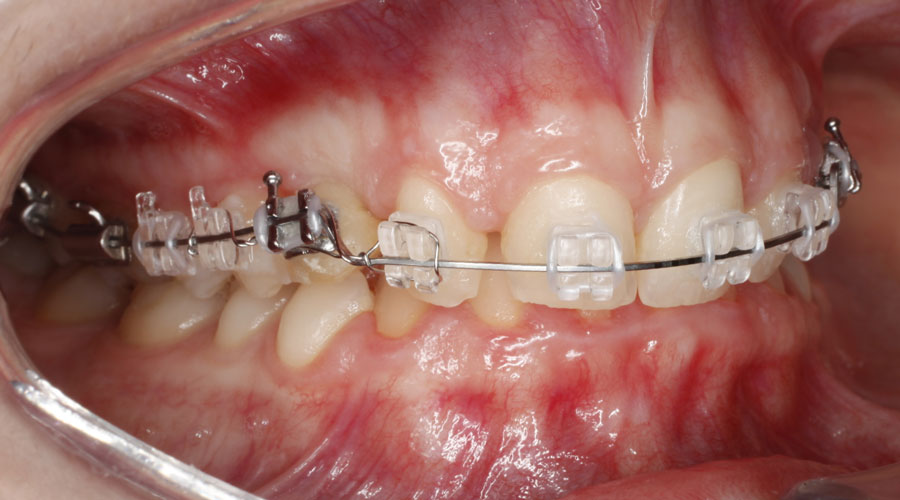

Caso clínico 2. La paciente presentaba Clase II dentaria división 2ª, con gran sobremordida, además de erupción ectópica de los caninos superiores. Se realizó ortodoncia multibracket transparentes con cirugía de fenestración de ambos caninos. Debido a la posición de éstos por palatino, colocamos dos microtornillos para ayudarnos en su tracción y poder separar la corona de las raíces de los incisivos. Posteriormente, traccionamos desde la cara vestibular con ayuda de un resorte para colocarlo en su lugar en la arcada.